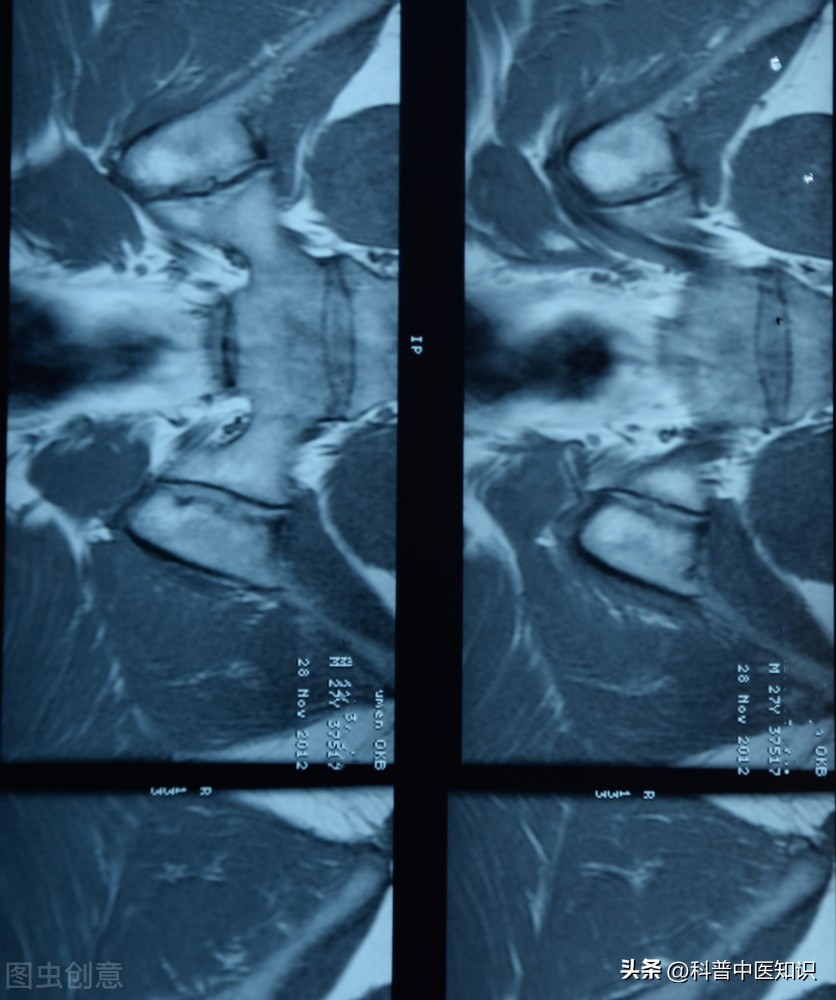

下面是著名中医焦树德教授的一则医案:一男20岁,患者半年前自觉腰髋部及双膝关节疼痛,遇热则痛减,伴僵直不舒。曾于当地医院查血沉70mm/h。予以青霉素、链霉素和炎痛喜康片等治疗无效。近日来腰髋关节痛加重,坐时尤著,腰椎僵直感明显,前弯、侧弯、后仰活动受限,双下肢无力,不能下床活动,生活不能自理。遂收入院治疗。入院后查血沉45mm/h,类风湿因子(-)。腰骶椎正侧位片示:两侧骶髂关节改变符合强直性脊柱炎。查体:腰椎旁压痛(+),腰背肌肉呈板状僵硬,双下肢肌肉萎缩,不能下地行走。舌质淡,舌苔白,脉细滑,诊断为强直性脊柱炎。

强直性脊柱炎过去被认为是类风湿关节炎的一个临床类型。后来发现,HLA-B27阳性的人群易患此病,证明了本病是一个独立的疾病。本病起病迟缓,以持续性腰或涉及胸、颈段脊柱疼痛,晨僵,活动受限,甚则出现驼背、脊柱强直、骶髂关节受损,两腿活动受限等,为主要症状的疾病。强直性脊柱炎的发病男性多于女性,且易多见于15—40岁左右的青少年及中年人。实验室检查90%以上的患者HLA—B27阳性。X线拍片显示:骶髂关节融合。对强直性脊柱炎的治疗,焦树德教授有自己独特的见解。

通过治疗,大量患者不但症状能够解除,而且不少病例通过坚持服用中药1—2年能使X线片子的结果,由骶髂关节融合改变为正常。